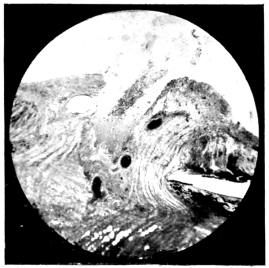

PLATE III.

16.

ABUNDANT EXUDATE INTO VITREOUS CAVITY

curly bracket span

42

17.

LENS FIRMLY FIXED BY ORGANIZED EXUDATE

18.

LENS FIRMLY FIXED BY ORGANIZED EXUDATE, BUT IN UNUSUAL POSITION

19.

TOTAL DETACHMENT OF RETINA, WITH CYST FORMATION

20.

RECLINED LENS LYING IN FRONT OF THE HYALOID BODY

21.

RECLINED LENS LYING IN FRONT OF THE HYALOID BODYxii